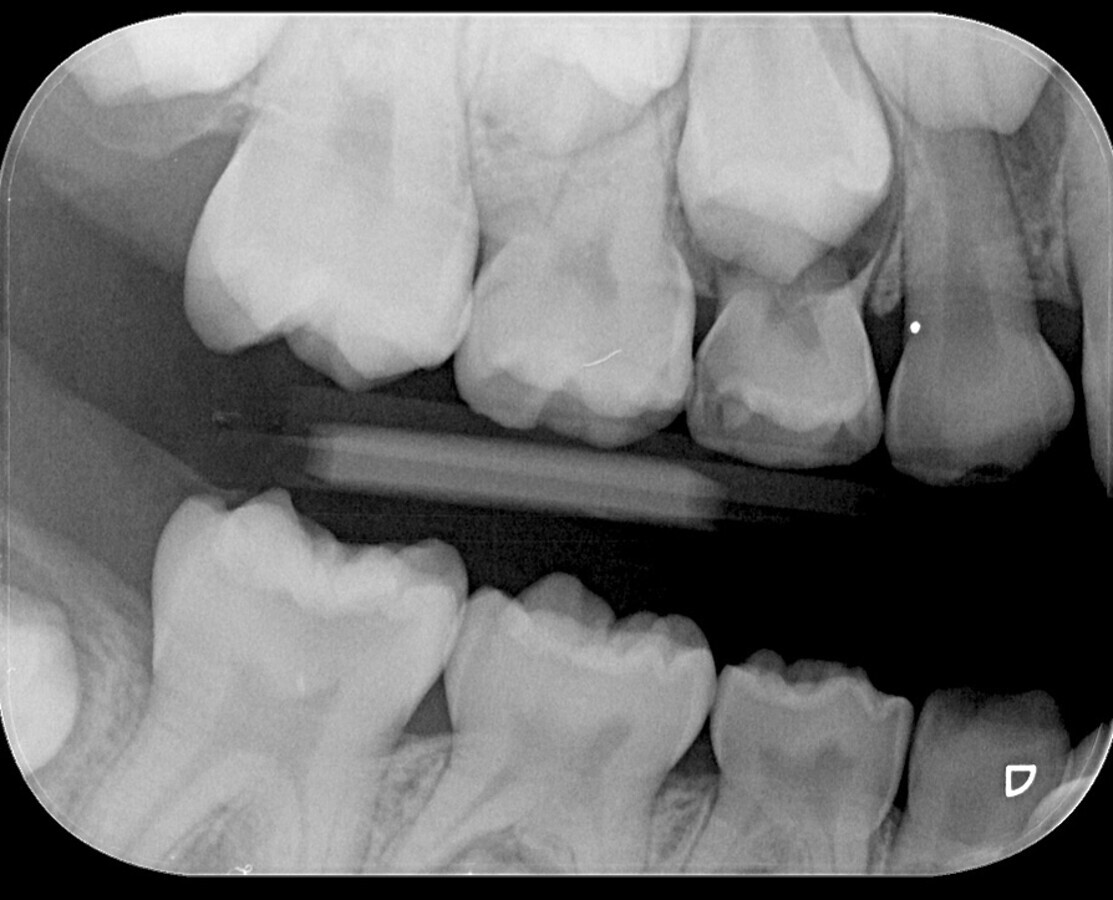

Al realizar el examen clínico, el diente 46 presenta una sombra subyacente en la dentina apreciada desde oclusal (Fig. 1), que al manejar el sistema internacional de detección y valoración de caries dental se considera una lesión ICDAS 4 (sombra subyacente en la dentina con esmalte aparentemente intacto). El examen radiográfico, con una exposición de aleta de mordida, evidencia una imagen radiolúcida que alcanza al tercio medio de la dentina (Fig. 2).

Fig. 2. El examen radiográfico evidencia una imagen radiolúcida que alcanza al tercio medio de la dentina.